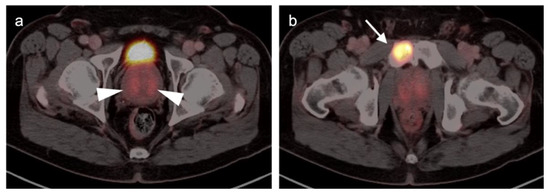

2.6. Vulvar Carcinoma